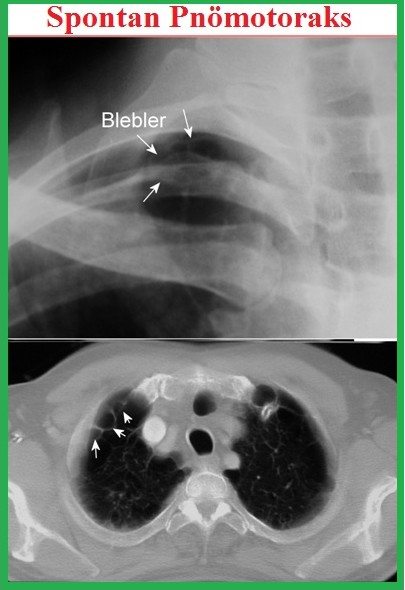

Etyoloji: Tam açıklanamamış. En çok sorumlu sebep bleb veya büllerin rüptürüdür. Amfizeme benzer değişiklikler (emphysema like changes “ELCs”) olarak tanımlanır. Torakotomi veya torakoskopide ELCs veya rüptürü %76-100 görüldüğü bildirilmiş. Genellikle üst lobun apikaline lokalizedirler.

Bleb: Visseral plevra yaprakları arasında hava toplanmasıdır. Parankim santraline doğru ilerleme göstermezler. Gaz değişimi veya pulmoner fonksiyonlar üzerinde minimal bir etki pnömotoraksa neden olabilir. Sağlıklı gençlerde normal akciğerin apikal kısımlarında yerleşirler. KOAH da multipl ve diğer akciğer kısımlarında da olabilir.

Toraks BT: kesin tanı koydurucu bir yöntemdir. Daha duyarlıdır. Blebleri gösterir, PSP’lilerin %89’unda vardır. Plevral efüzyon pnömotoraksların %10-20’sinde gelişebilir.